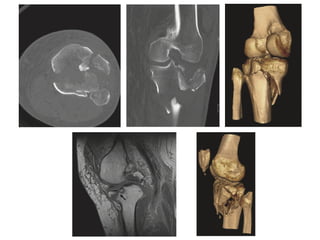

close fracture left tibia

plateau with left proximal

fibula fracture

• CT scan: help surgical planning, more reliability of classifying the

fracture and deciding on a treatment plan

• MRI: additional information about injuries to the soft tissue

close fracture lefttibia plateau with left proximal fibula fracture